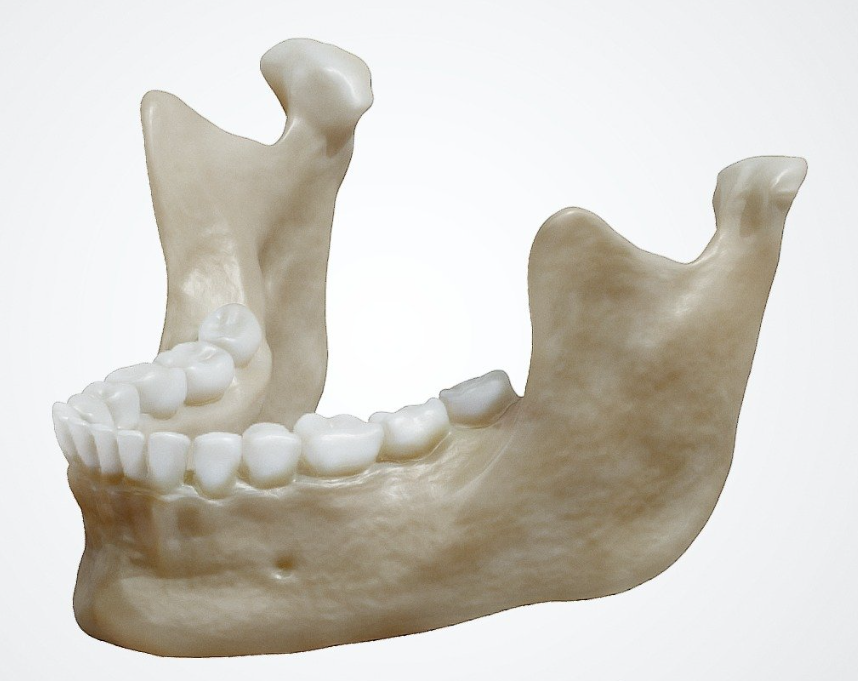

mandible bone anatomy 3D illustrationI. Vue d’Ensemble : Qu’est-ce que la Mandibule ?

La mandibule, ou maxillaire inférieur, est un os impair, médian et symétrique, situé à la partie inférieure de la face. C’est le seul os mobile de la face ; il s’articule de chaque côté avec l’os temporal par l’intermédiaire des articulations temporo-mandibulaires (ATM).

Sur le plan morphologique, la mandibule est constituée de trois parties principales :

- Le corps (arc mandibulaire)

- Les deux branches montantes (droite et gauche)

Cette architecture lui confère une forme caractéristique en fer à cheval, facilement reconnaissable dès les premiers cours d’anatomie.